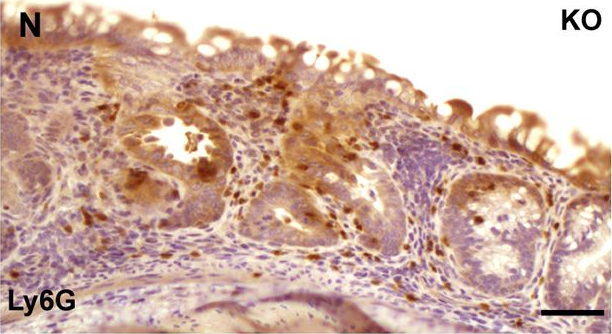

Our findings reveal that the therapeutic efficacy of phage treatment is critically dependent on the presence of neutrophils, which act synergistically with phages to achieve effective bacterial clearance, particularly when bacterial burden exceeds a defined threshold. Alveolar macrophages, however, do not significantly contribute to infection resolution in vivo.

Since neutrophils play a key-role in supporting phage-mediated Pseudomonas clearance, the efficacy of phage therapy is closely linked to the hosts immune competence - an important consideration when treating immunocompromised patients.